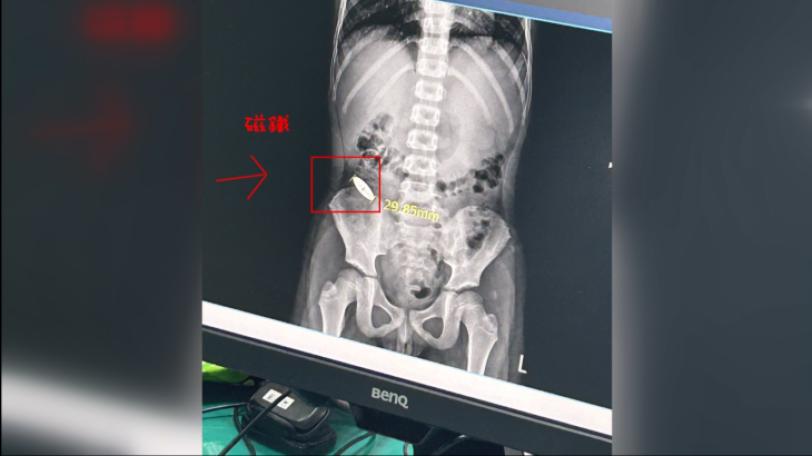

臺南補習班學生霸凌 逼6歲囡仔吞3公分吸石

|台語新聞頂日仔臺南市安南區一間補習班,學生之間發生衝突,講有一个11歲的囡仔逼一个6歲的囡仔共一个3公分長的吸鐵吞落去,到今吸鐵猶佇體內。這層代誌補習班煞無主動通報,是家長共學校老師講,這件代誌才煏開,教育局經過稽查發現,這間補習班有3項違規,會依法罰錢,嘛要求改善。(新聞標題、導言為台語文)